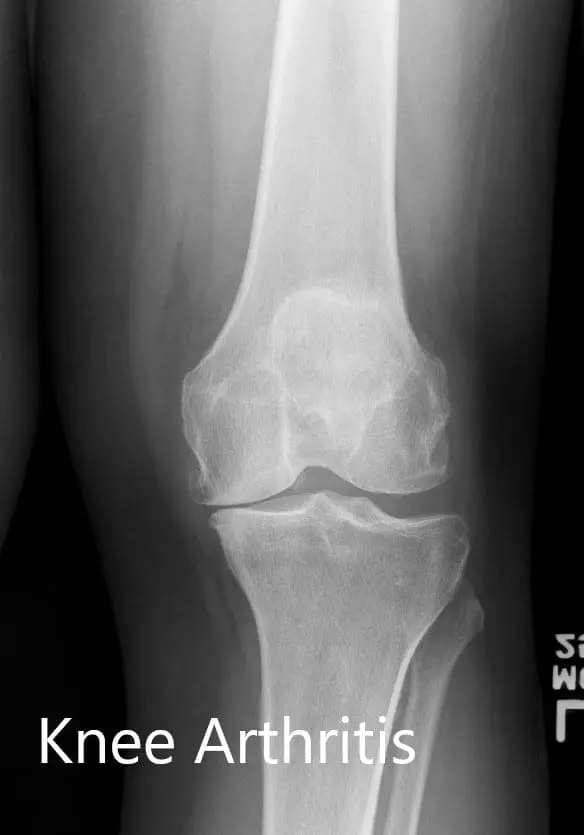

Preoperative X-ray of the left knee showing AP and lateral views

Preoperative X-ray of the left knee showing AP and lateral views - img 2